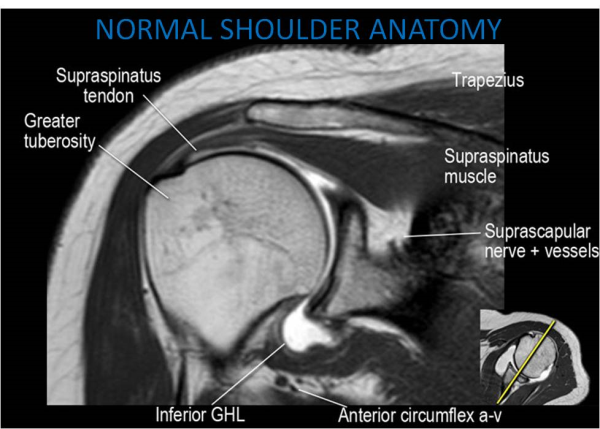

Glenohumeral ligament: анатомия и функции плечевого сустава